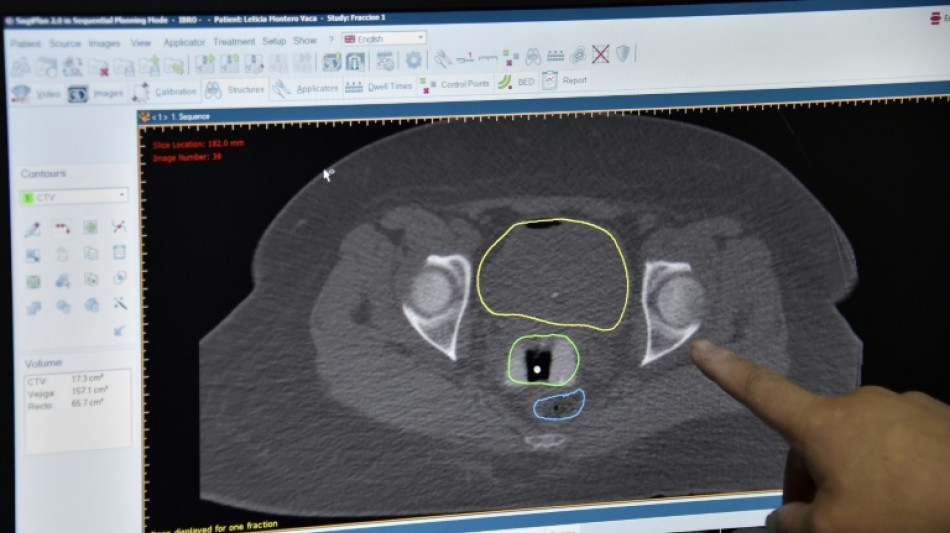

New cancer plan urged as survival improvements in England slow / Photo: © AFP